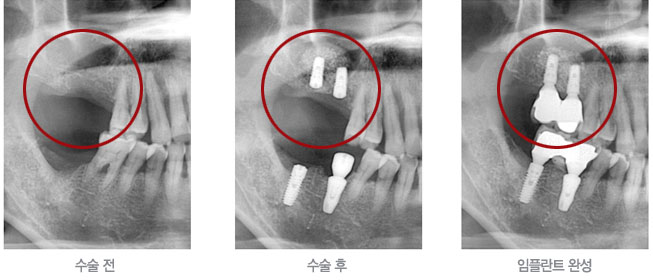

치료증례

저희 의원은 환자의 동의를 얻은 사진만 기재됩니다.

위 어금니 발치 후 변화